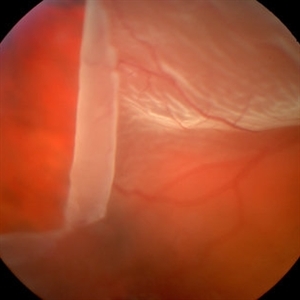

Giant Retinal Tear

Mar 1 2014 by Homayoun Tabandeh, MD, FASRS

Giant retinal tear with radial element and rolled back posterior edge.

Condition/keywords: retinal tear